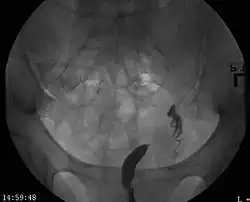

- Clase V: Útero Particionado (Septum uterino o partición).

- Los dos conductos Mullerianos están fusionados pero la separación entre ellos todavía está presente, separando el sistema en dos partes. Con un septum completo la vagina, el cérvix y el útero se pueden separar. Usualmente el septum afecta solo la parte craneal del útero. Un septum uterino es la malformación uterina más común y la causa de muchos abortos espontáneos. Es diagnosticado por técnicas de imágenes médicas como ecografía o resonancias magnéticas (MRI por sus siglas en inglés). La resonancia magnética (MRI) es considerada la mejor herramienta de diagnóstico debido a sus capacidades de multiplanos así como también su habilidad de evaluar el contorno uterino, zona nodal, y otras anatomías pélvicas. Un histerosalpingograma no es considerado de utilidad debido a su inhabilidad para evaluar el contorno exterior del útero y distinguir entre un bicornio y un útero particionado.

Un septum uterino puede ser corregido con una histeroscopia.

Aparte del examen físico, el doctor necesitará tomar imágenes para determinar las características de la malformación: Ultrasonografía ginecológica, resonancia magnética (MRI) pélvica o histerosalpingografía. Un histerosalpingograma no es considerado de utilidad debido a su inhabilidad para evaluar el contorno exterior del útero y distinguir entre un bicornio y un útero particionado. Adicionalmente una laparoscopia y/o histeroscopia pueden ser recetados. En algunos pacientes el desarrollo vaginal puede ser afectado. Al contrario de lo que pudiera pensarse, esta "malformación" no representa incomodidad alguna para la persona que la presente.